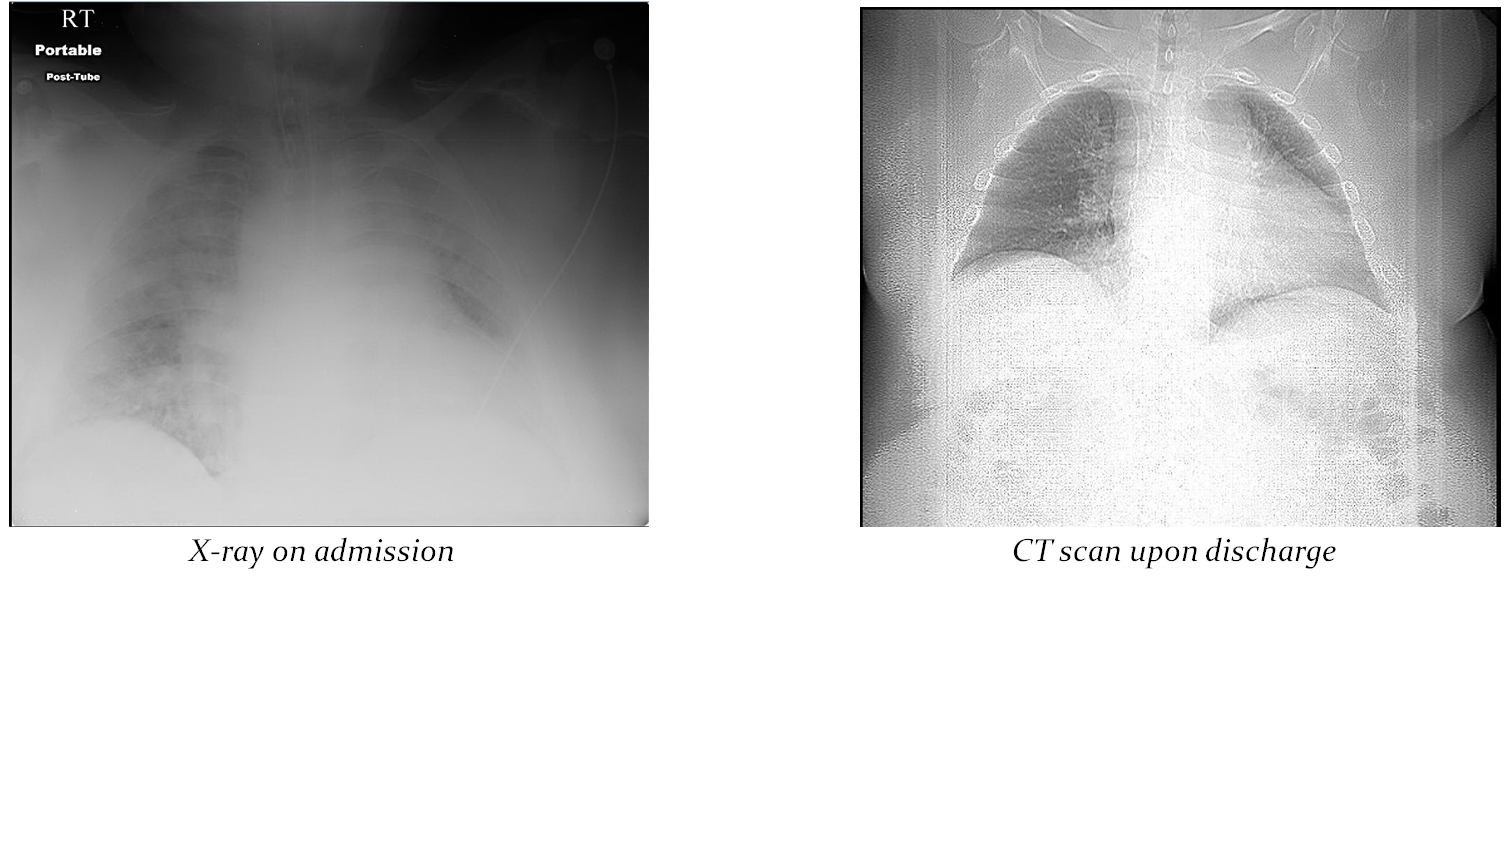

Case Presentation: A 54-year-old morbidly obese male, with a history of asthma, hypertension, bilateral knee replacement and tobacco abuse was found unresponsive outside his home on Christmas Eve. EMS brought him with severe hypercapnic respiratory failure pC02 99.7, white count 21 X 103/mcL, cocaine screen positive and blood ethanol level of 0.230 g/dl. Initial chest x-ray demonstrated bilateral interstitial and airspace consolidation. The patient was intubated and started on coverage for aspiration pneumonitis. Sputum cultures were positive for 1+ Enterobacter cancerogenus and 1+ Pantoea agglomerans. Oerskovia species were reported in 2 of 2 sets of blood cultures. Susceptibilities were sent to an outside lab for further study. Literature review of preliminary culture results linked this bacterium to prosthetic material infections. Bactrim was initiated and knee x-ray found a small right knee effusion.

The patient’s mental status improved, and he was successfully extubated. Antibiotics were modified with the addition of Ampicillin-Sulbactam. The patient was transferred to the medical floor and was discharged with last memory of drinking one bottle of tequila at a Christmas party before coming to the hospital.